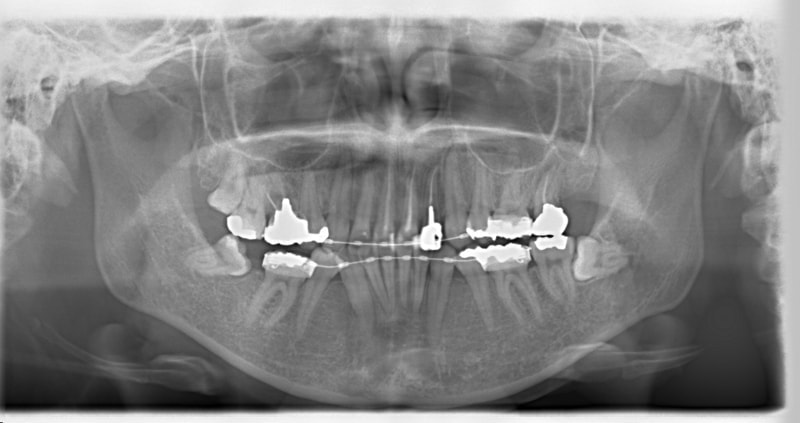

治療前

治療開始時